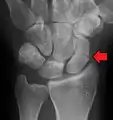

Radiolucency around a 12 days old scaphoid fracture that was initially barely visible.[13]

Scaphoid fractures are often diagnosed using plain radiographs and multiple views are obtained as standard.[9] However, not all fractures are apparent initially.[7] In 1/4 of cases, the clinical examination suggests a fracture, but the X-ray does not show it, even though there is indeed a fracture.[10] Therefore, people with tenderness over the scaphoid (those who exhibit pain to pressure in the anatomic snuff box ) are often splinted in a thumb spica for 7–10 days at which point a second set of X-rays is taken.[7] If a minimally displaced fracture was present initially, healing will now be apparent. Even then a fracture may not be apparent. A CT Scan can then be used to evaluate the scaphoid with greater resolution. The use of MRI, if available, is preferred over CT and can give one an immediate diagnosis.[11] Bone scintigraphy is also an effective method for diagnosis fracture which do not appear on Xray.[12]